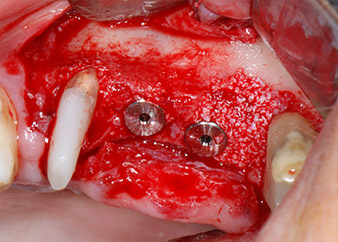

Dann wurden die Implantate (Restore, Keystone Dental) mit dem Implantatmotor eingesetzt (Abb. 11 und 12).

Insertion des Implantats an Position 26

Abb. 11: Insertion des Implantats an Position 26 bei geringer Geschwindigkeit und einer Drehmomentbegrenzung von 35 Ncm.

Eindrehen der Abdeckschrauben

Abb. 12: Beide Implantate sind in Position und bereit für das Eindrehen der Abdeckschrauben.